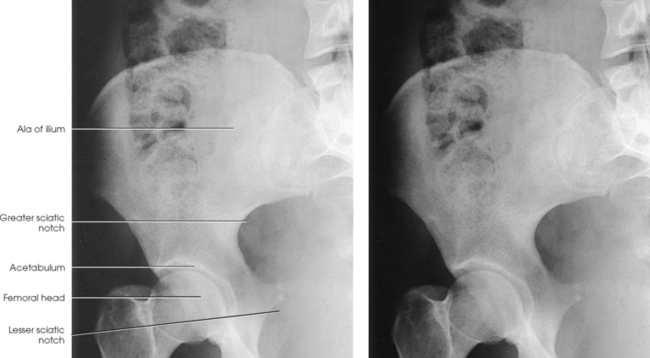

The ilium consists of a body and a broad, curved portion called the ala. The body of the ilium forms approximately two fifths of the acetabulum superiorly (Fig. 7-3). The ala projects superiorly from the body to form the prominence of the hip. The ala has three borders: anterior, posterior, and superior. The anterior and posterior borders present four prominent projections:

The anterior superior iliac spine (ASIS) is an important and frequently used radiographic positioning reference point. The superior margin extending from the ASIS to the posterior superior iliac spine is called the iliac crest. The medial surface of the wing contains the iliac fossa and is separated from the body of the bone by a smooth, arc-shaped ridge, the arcuate line, which forms a part of the circumference of the pelvic brim. The arcuate line passes obliquely, inferiorly, and medially to its junction with the pubis. The inferior and posterior portions of the wing present a large, rough surface—the auricular surface—for articulation with the sacrum. This articular surface and the articular surface of the adjacent sacrum have irregular elevations and depressions that cause a partial interlock of the two bones. The ilium curves inward below this surface, forming the greater sciatic notch.

The ischium consists of a body and the ischial ramus. The body of the ischium forms approximately two fifths of the acetabulum posteriorly (see Figs. 7-2 and 7-3). It projects posteriorly and inferiorly from the acetabulum to form an expanded portion called the ischial tuberosity. When the body is in a seated-upright position, its weight rests on the two ischial tuberosities. The ischial ramus projects anteriorly and medially from the tuberosity to its junction with the inferior ramus of the pubis. By this posterior union the rami of the pubis and ischium enclose the obturator foramen. At the superoposterior border of the body is a prominent projection called the ischial spine. An indentation, the lesser sciatic notch, is just below the ischial spine.